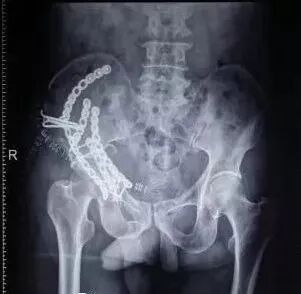

1)股骨近端(股骨头,颈,转子部位)

图片

• <65岁,内固定;>65岁,关节置换

• 患者全身情况稳定,应早期内固定。

• 内固定方式很多,如DHS,pfna等。